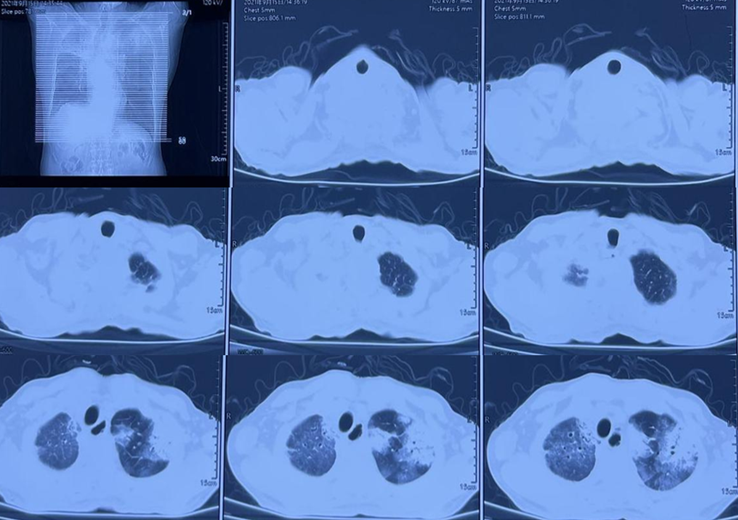

图1~2为COP患者,图1表现为双肺实变,图2为大片实变,患者快速进展为呼吸衰竭。

图1  COP患者胸部CT

图2  COP患者胸部CT进展